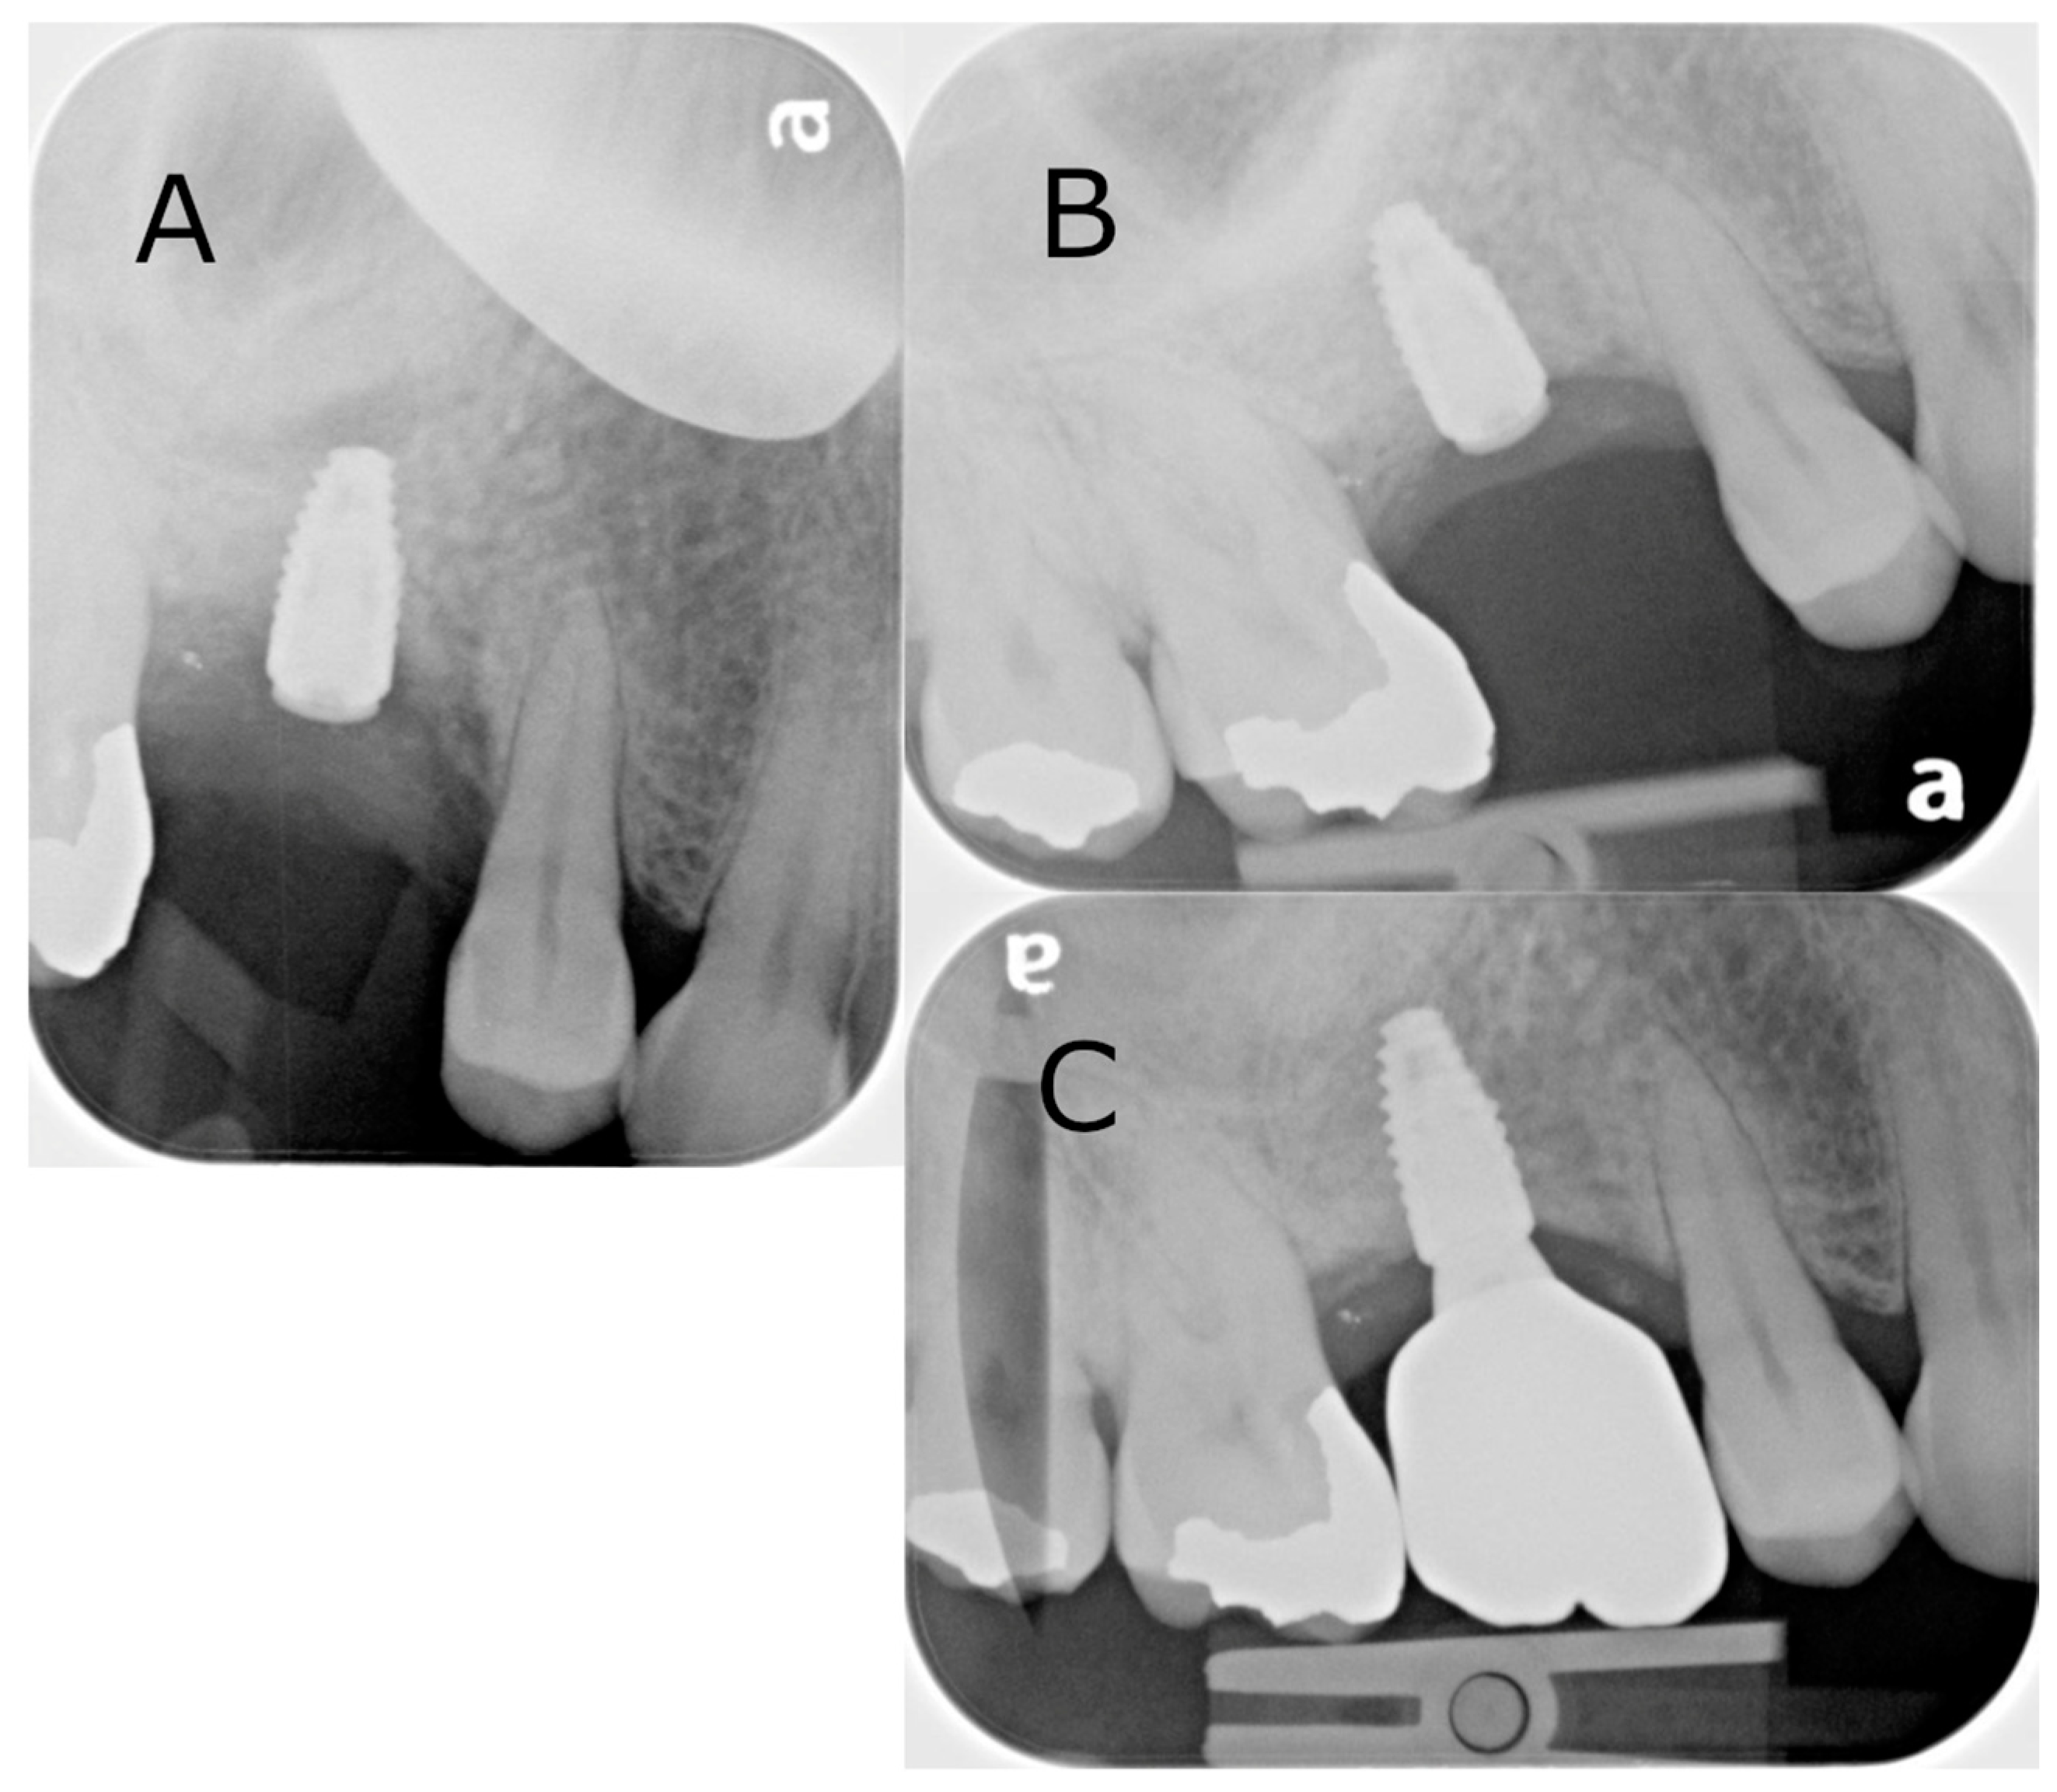

A 64-year-old male patient presented with a complaint of a missing upper right first molar that had been extracted 12 months prior. A CBCT was taken, and restoration with an implant was recommended with lateral sinus augmentation due to the available bone being 3.2 mm in depth (Figure 3A). A surgical treatment plan was formulated, which included a surgical guide to aid in the outline of the bony window and simultaneous implant placement. Consent was obtained from the patient prior to the commencement of the procedure. Local anaesthesia with 4% articaine containing 1:100,000 adrenaline was administered at the buccal and palatal regions of the surgical area. A full thickness flap elevation was performed. The surgical guide was used to direct the lateral window preparation of the sinus wall (Figure 3B,C). The surgical guide sat flush to the cortical plate and dentition. The opening was first outlined and then widened with the piezoelectric diamond burs and round burs from the Lateral Window Bur Kit (Acteon, Lyon, France). Linear osteotomy cuts were performed with rotatory instruments and piezoelectric devices. The resulting window of the sinus wall was reflected superiorly with the mucosa elevated. Simultaneous implant placement and grafting were then performed due to the presence of a satisfactory amount of residual bone. A single Ø 4.1 mm × 10 mm bone level Roxolid SLActive implant (Straumann, Basel, Switzerland) was placed in the preplanned osteotomy site, with Bio-Oss granules and a Bio-Gide membrane (Geislitch, Wolhusen, Switzerland) placed in the sinus cavity (Figure 3D). The full thickness flap was re-approximated with PROLENE suture 5-0 (Ethicon, Raritan, NJ, USA) placed. Typically, three months are required for osseointegration prior to rehabilitation with an implant-supported prothesis, while this may be increased to six months when lateral sinus augmentation is performed at the same appointment. In this case, the surgical site was reviewed six months post-operatively, confirming successful osseointegration and the absence of complications (Figure 4B). The crown was placed at a separate appointment, two months later (Figure 4C).

Figure 4. Intraoral radiographs of the surgical site from the lateral sinus lift with simultaneous implant placement: (A) immediately post-operatively following the implant placement; (B) six-month follow-up; (C) crown placement. Note that the letter “a” is pre-printed on the phosphor storage plate upon acquisition, serving as a reference for orientation.